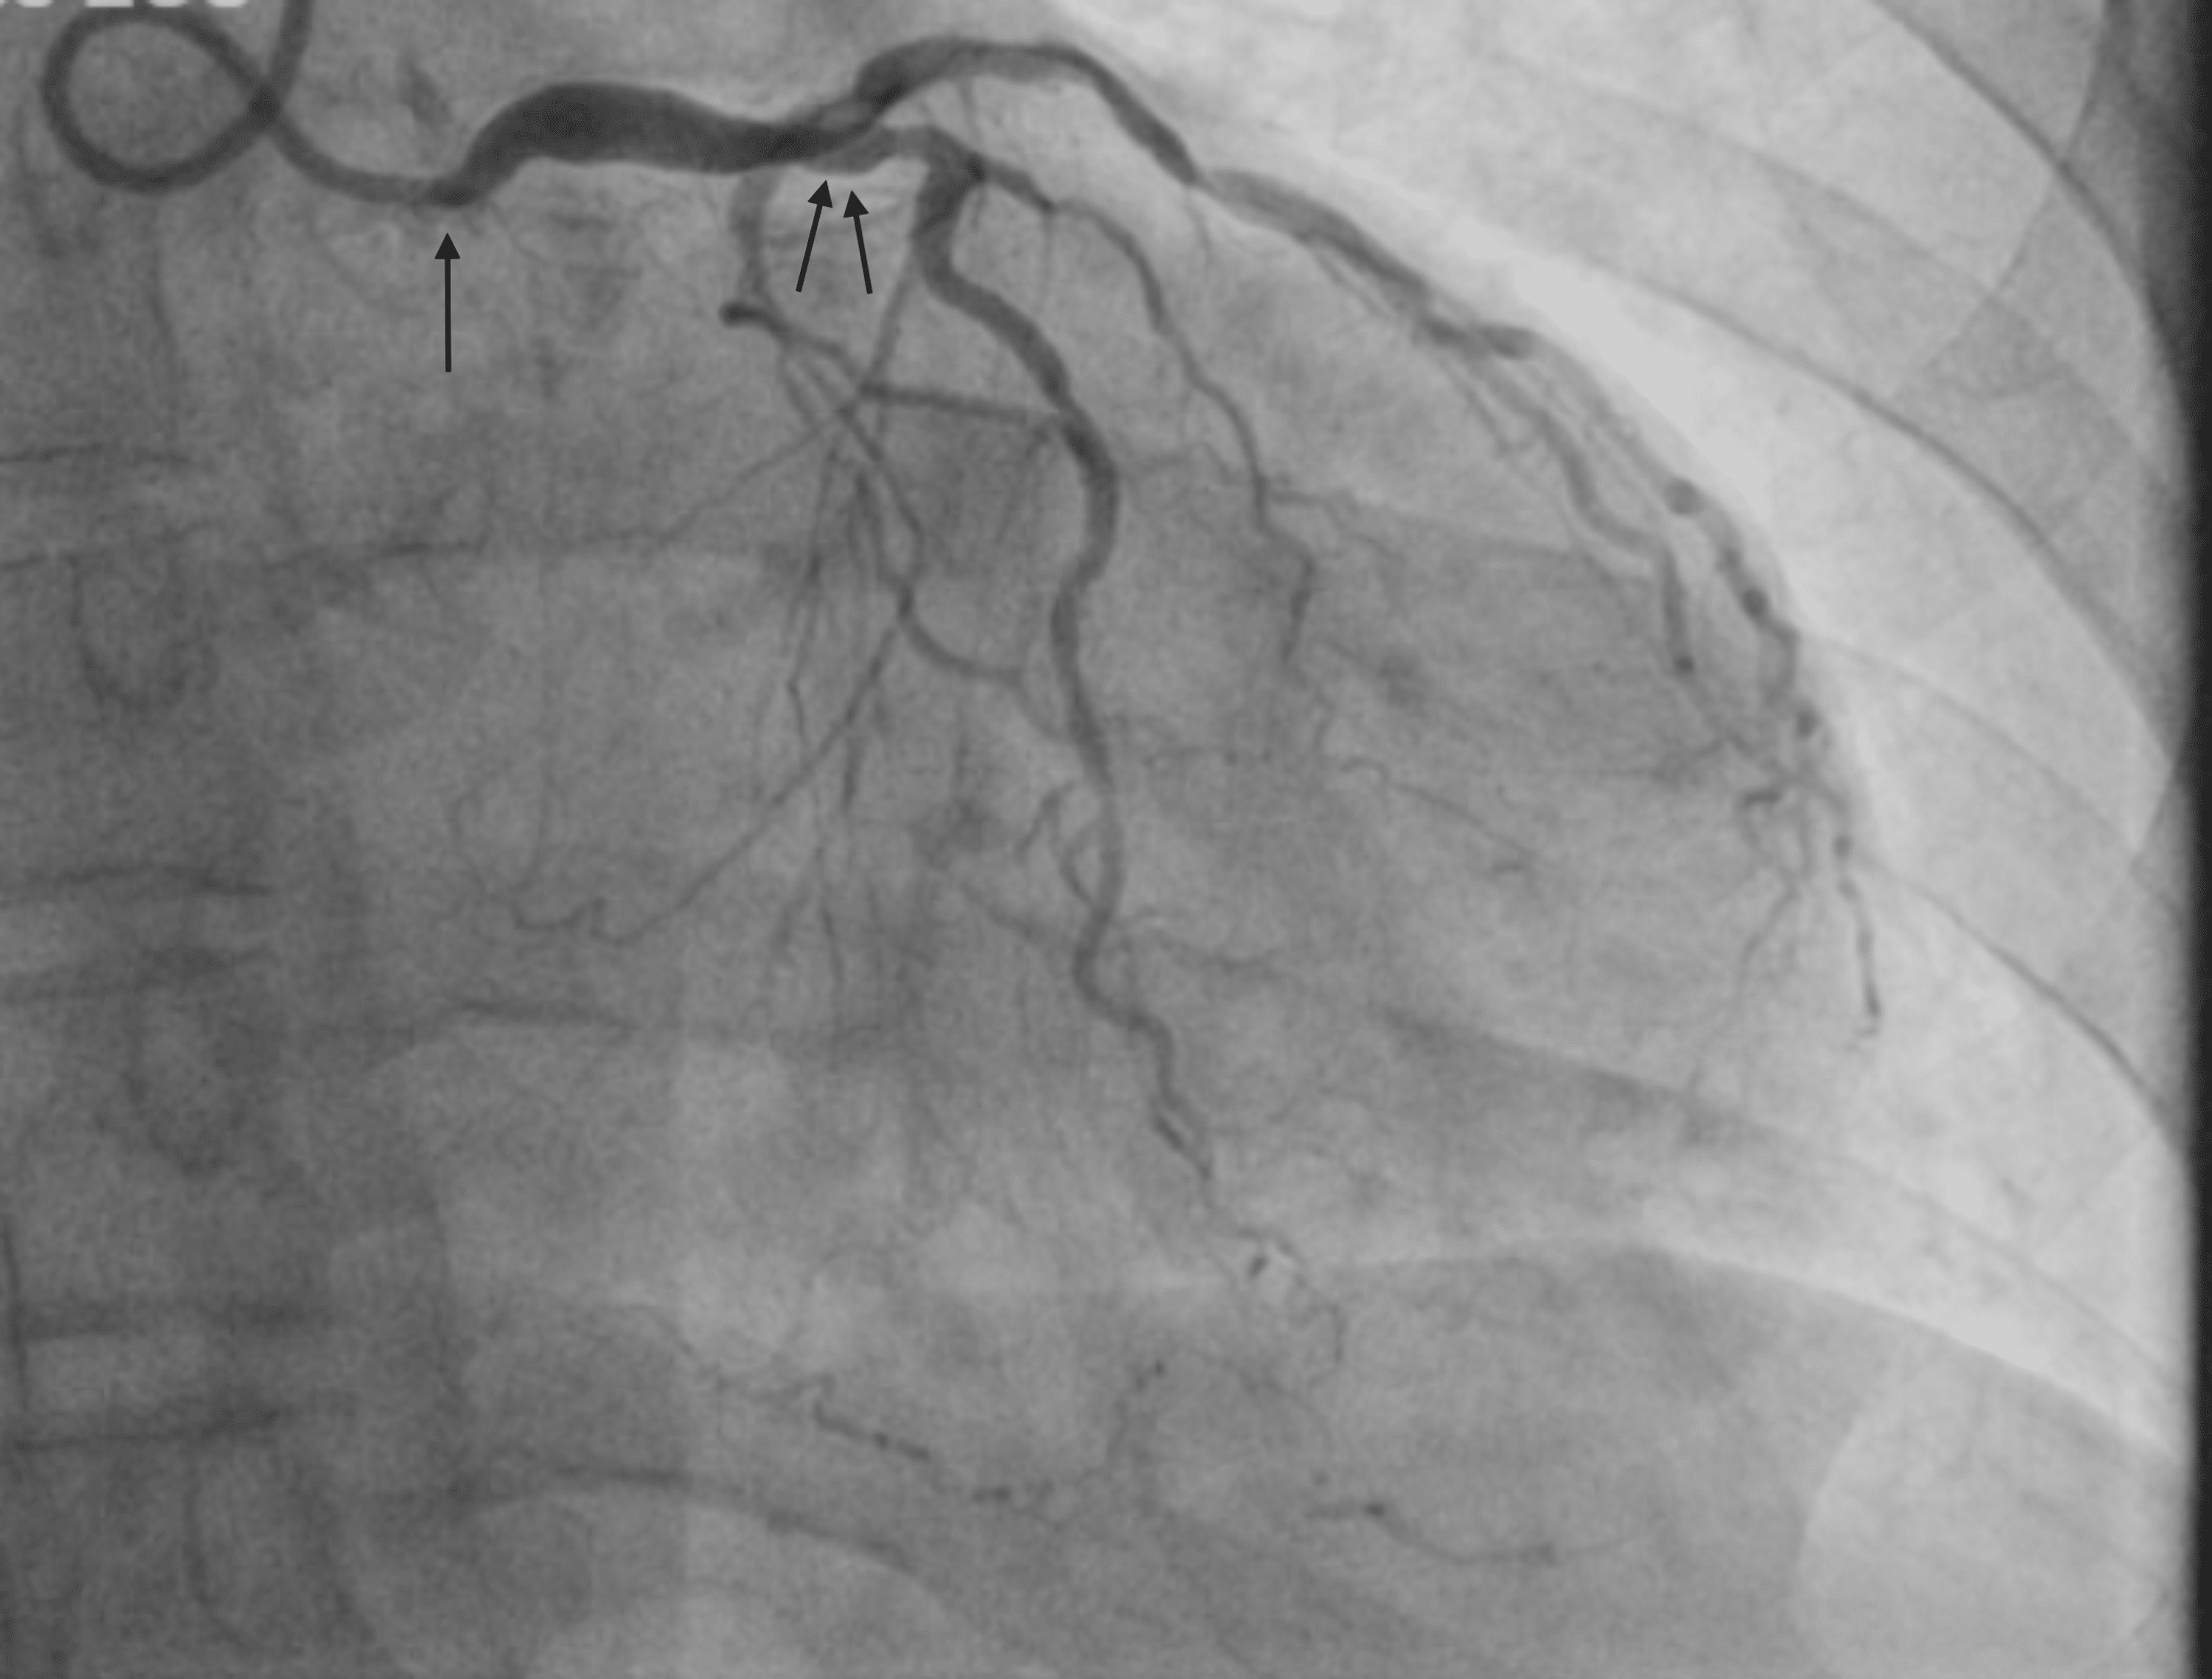

Left heart catheterization revealing right coronary artery collaterals

Left heart catheterization revealing right coronary artery collaterals Heart Catheterization Nerve Damage In this study, we report the incidence of this. Review the complications of cardiac. Identify the technique of cardiac catheterization. Neuropathy is a rare, but potentially morbid, complication of cardiac catheter ization. The nerve may be injured by needle puncture, or by compression from hematoma, pseudoaneurysm, hemostasis devices, or by. The transradial access site is currently the gold standard for. Heart Catheterization Nerve Damage.